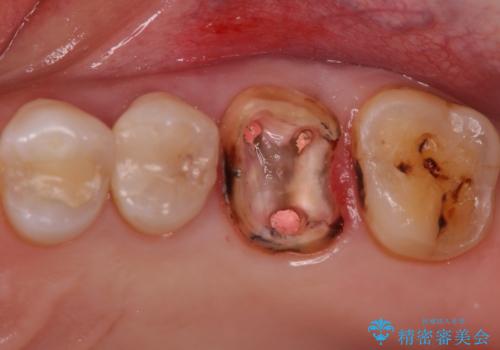

- 検査の結果被せ物の下に虫歯が確認された患者様です。

虫歯を取りきった後セラミッククラウンでの修復処置を行います。

- 左上6/仮歯+ジルコニアクラウン:11,000円+110,000円 (根管治療:保険)費用は治療当時の料金となります

被せ物の裏側の虫歯は被せ物を取らないと除去できません。

今回は過去に治療された部分をすべてやり直しました。

再治療にならないような精密な治療が重要です。